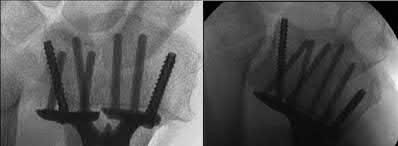

Question 19

A 28-year-old male sustains a closed comminuted tibial shaft fracture.

Two hours post-injury, he develops severe leg pain unyielding to narcotics. His blood pressure is 120/80 mmHg. Intracompartmental pressure monitoring is performed. Based on current guidelines, which measurement dictates an emergent 4-compartment fasciotomy?

Explanation

Acute compartment syndrome is classically defined by tissue hypoperfusion. The absolute compartment pressure is less reliable than the differential pressure (Delta P). A Delta P (Diastolic Blood Pressure minus Compartment Pressure) of less than 30 mmHg is an absolute indication for emergency fasciotomy, as capillary perfusion gradient is lost when tissue pressure approaches the diastolic pressure.